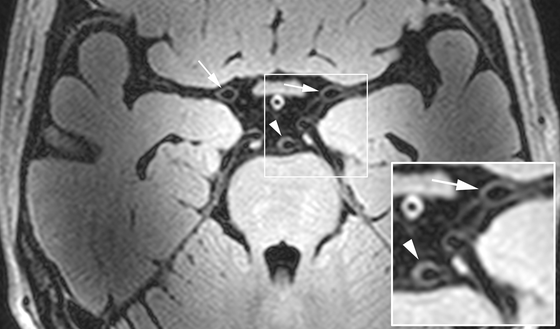

The UMC Utrecht Center for Image Sciences is world leading in the development of innovative MRI brain imaging methods at high and ultra-high MRI field strength (3Tesla and 7Tesla MRI; 9.4 Tesla preclinical MRI). Newclinical and preclinical high-field imaging methods allow the detailed assessment of the brain tissue (micro infarcts) and the arterial vasculature including highly detailed vessel wall imaging. Other unique methods at  ≥ 7Tesla are highly detailed MR imaging of the hippocampal subregions and MR spectroscopy (glutamate) and functional MRI of cortical gray matter layers and detailed assessment of the cerebrovascular reserve both with BOLD MRI and ASL MRI methods. Furthermore, together with the group of Prof. Max Viergever special focus is on the quantitative assessment of the brain with DTI analysis and the volumetric analysis of brain (sub) regions including the hippocampus, white matter lesions, microbleeds and smaller and larger infarcts.